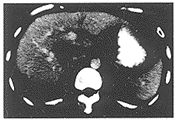

图1 开始注射造影剂25秒后肿瘤明显强化

门脉期75秒,肿瘤实体造影剂潴留仍较高,密度80~100HU,肝实质密度也达85~110HU,是门脉期充盈高峰期,因而,两者密度平均差值最高-5.4。而100秒,尽管肝癌实体密度降低,但肝正常组织密度也继续减低,密度平均差值为-11。90秒,肝实质密度仍维持较高水平,此时肿瘤实体密度迅速减低,密度平均差值最低为-15.7(见图2)。

图2 自注射造影剂90秒后肿瘤实体呈低密度